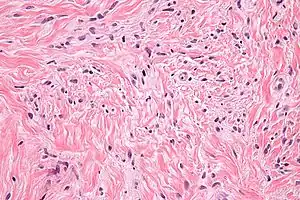

| Micrograph of mammary myofibroblastoma. H&E stain. | |

a)Mammary-type myofibroblastoma b) positive for CD34 c) and desmin

a)Mammary-type myofibroblastoma b) positive for CD34 c) and desmin Intermed. mag. Mammary myofibroblastoma

Intermed. mag. Mammary myofibroblastoma High mag. Mammary myofibroblastoma

High mag. Mammary myofibroblastoma

Medical imaging may suggest but cannot prove that a tumor is MFB. Mammography, computed tomography scans, and magnetic resonance imaging of mammary[1][12] and extramammary[1][13] MFB typically show well-defined and well-circumscribed tumors which in almost all cases have no calcifications; these results suggest that the tumor is not malignant but do not indicate which type it might be. The diagnosis of MFB depends on the microscopic histopathology (i.e. appearances after proper tissue preparation and staining) of its pre-surgery biopsied issues. As shown in the upper image and the two images in the Additional images section seen below, both mammary and extramammary MFB tissues contain spindle cells, variable numbers of adipocytes (i.e. fat cells) and broad sheets or, less often, thick bundles of collagen fibers.[5] About 4% of cases have an epithelial tumor cell-like morphology,[5] i.e. the tissues are composed predominantly of epithelioid cells variably mixed with a minority (10% to 40%) of round, polygonal, and spindle-shaped cells.[19] Unlike malignant tumors, MFB tumors do not have: a) atypical cells except in the rare cases which contain small clumps of multinucleated cells; b) rapidly proliferating cells as defined by measuring the proliferative index (i.e. fraction of cells undergoing mitosis); or c) areas of necrosis (i.e. areas of dead or dying cells).[16] Microscopy of tumors in the spindle cell lipoma tentative variant of MFB show a mixture of mature fat cells, ropey collagen, and spindle cells in a myxoid (i.e. background connective tissue that stains blue or purple rather than the red of normal connective tissue) matrix.[18] The blood vessels in these tumors often appear hyalinized.[16] Tumor tissues in the tentative cellular angiofibroma variant of MFB contain spindle cells in all cases, fat cells in ~50& of cases, mast cells, peri-vascular infiltrates of lymphocytes, pleomorphic cells in some cases, and cells with some features of the malignant sarcoma cells in sarcoma tumors in rare cases. (The presence of these sarcoma-like cells does not seem to impact the prognosis of this variant.) All of these cells are in edematous-to-fibrous stromatous tissue.[16]